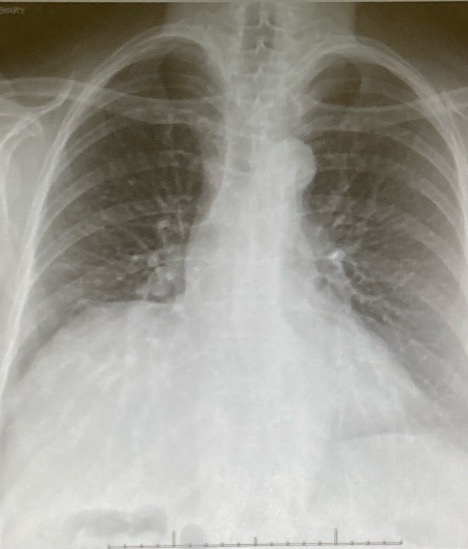

A 74-year-old female patient who was a former smoker with a history of breast cancer in remission presented to the thoracic surgery service (Figure 1) with a suspicious lung nodule. Further diagnostic imaging identified a 12 mm lesion in the S8 segment of the left lower lobe (Figure 2). Preoperative lung function showed both a forced expiratory volume in one second of 100 percent and a diffusing capacity of the lung for carbon monoxide of 104 percent. She had no other significant past medical history. The patient had a World Health Organization performance status of one and an American Society of Anesthesiology grade class two.

Figure 1: An image of the preoperative chest X-ray (CXR).